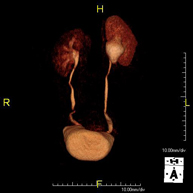

- Renal artery MRI angiography

A non-invasive diagnostic test that involves studying the renal arteries, obtaining high-definition anatomical images using an electromagnetic field and radio waves (with transmitter and receiver). The use of paramagnetic contrast (gadolinium) is essential. However, it is a radiation-free procedure. The quality of the images allows for 2D and 3D reconstructions. This test is recommended, for example, in patients suffering from refractory hypertension that does not respond to processing, in patients with kidney damage in order to obtain a pre-surgical ‘vascular’ map, etc.